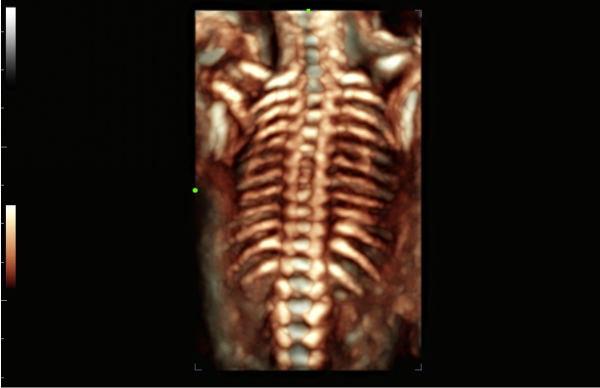

Galeria obrazÃģw